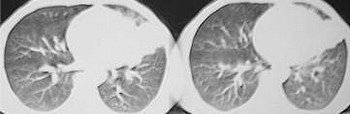

f,41,胸部痛3个月,近3天自述有咯血。胸痛前有感冒病史,未治疗。

补充最后3图分别为2mmhrct和后重建。

考虑:慢性节段性(左上叶下舌段)非特异炎症(炎性假瘤形成). 理由是:

1).实变周围有渗出性病变(见肺窗片);

2.)纵膈窗片见:垂直胸膜边缘平直甚至微凹;

3).邻近胸膜有侵犯,但仅轻度增厚及粘连,肋膈角正常(见重建片);

4).实变灶内密度失均,有少量短管状气影,可能为合并之支扩.